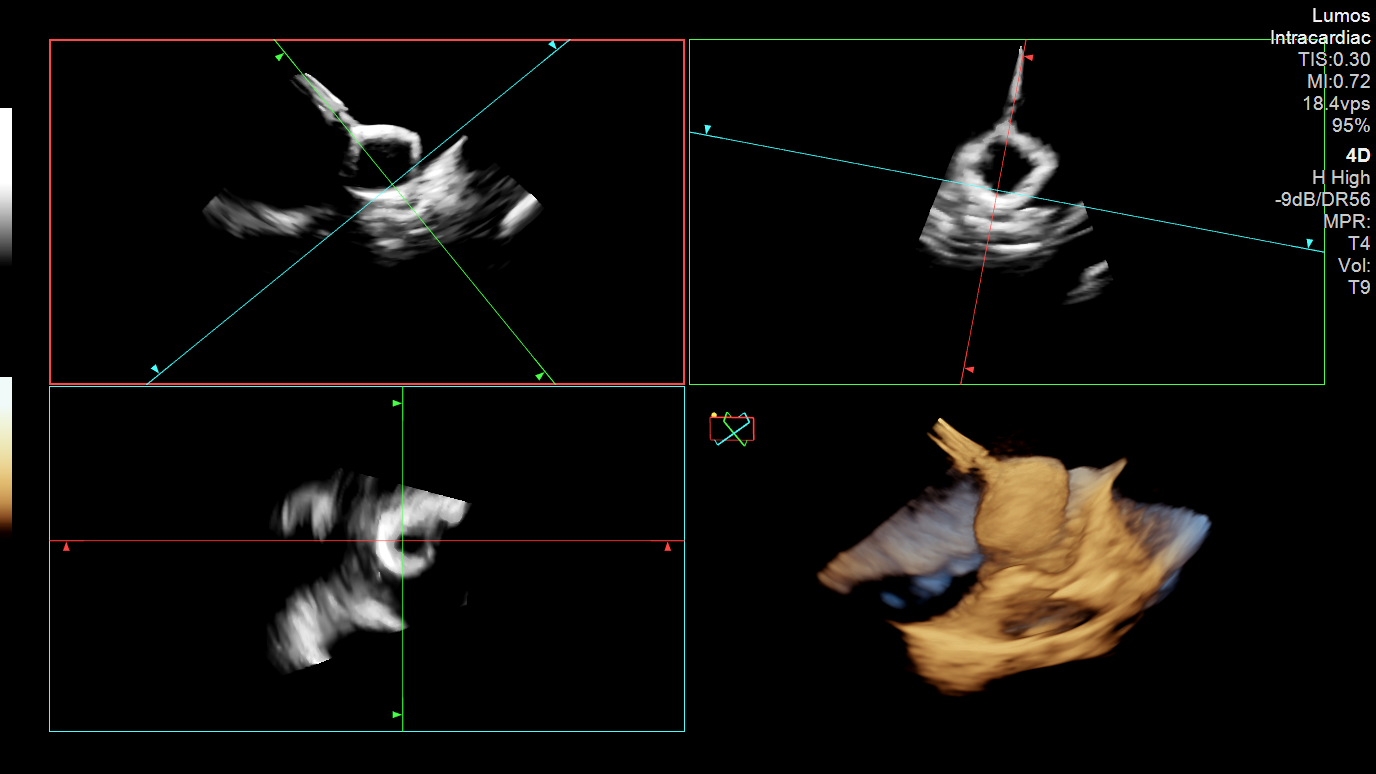

Biplane ICE guidance ensured safe, accurate transseptal sheath positioning into the LAA prior to device delivery (Figure 2). The LAAO device was inserted and guided into position with real-time 4D ICE visualization (Figure 3). Appropriate orientation and compression were confirmed, followed by a tension/tug test to validate stability.